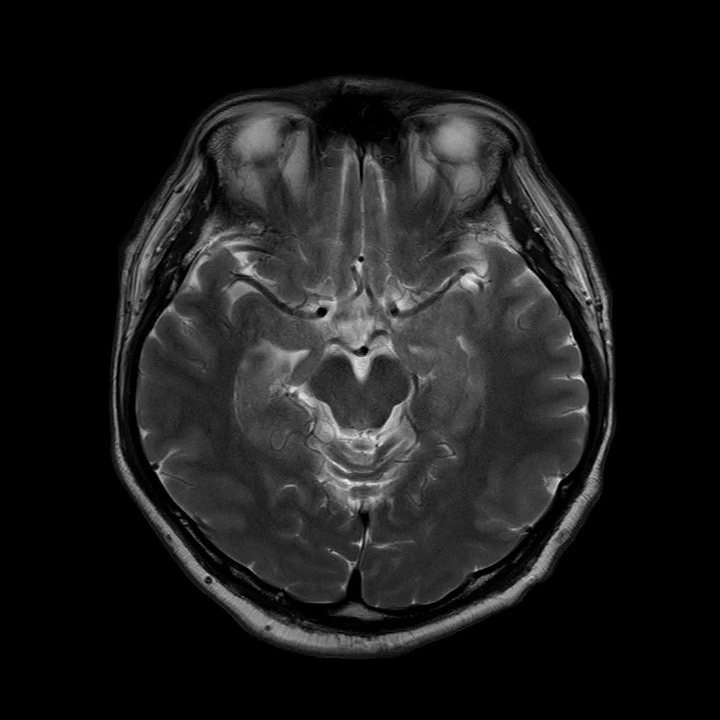

Brain MRI : 뇌 자기공명영상 - 뇌 구조 확인.

Diffusion MRI (급성기 뇌손상 확인을 위한 MRI),

Brain MRI (뇌 조직 자기공명영상),

Brain MRA (뇌혈관 자기공명영상),

Carotid MRA (좌우 경동맥 자기공명혈관촬영)

이렇게 여러 종류의 MRI 촬영을 했네요!

영상을 보면.. 위에서, 옆에서, 밑에서.. 여러 각도에서 입체적으로 찍었어요.

급성기 뇌송상은 일반 MRI에는 나타나지 않고,

Diffusion MRI에만 보이는 거라..

그것을 먼저 촬영하고..

과거 혈전이 있었는지 등은 일반 뇌 MRI로 확인하고..

처음 알았는데, 사진에서 왼쪽은 오른쪽이고, 오른쪽이 왼쪽이라네요.

3D로 뇌혈관, 심장으로부터 목으로 연결되는 경동맥도 잘 보이고,

내 뇌 구조가 이렇게 생겼구나! 정말 신기하더라고요!!

혈관 모습도 좌우 다 다르고 (당연한거지만 신기해서)

Brain MRI (Magnetic Resonance Imaging) : 뇌 조직 자기공명영상. 뇌 안쪽 구조를 사진처럼 찍어 큰 이상이 없는지 확인하는 검사.

Brain MRA (Magnetic Resonance Angiography) : 뇌혈관 자기공명영상. 뇌 속 혈관이 좁아졌거나 막혔는지, 이상 혈관이 있는지 보는 검사.